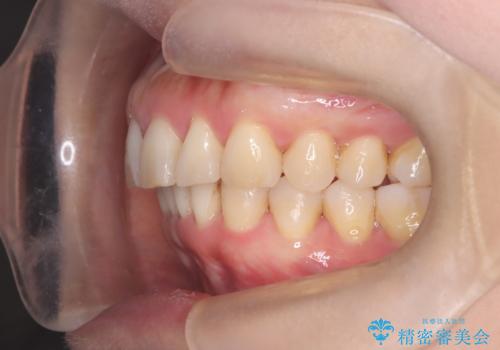

【インビザライン】出っ歯を治したい

- 前歯が出ていることを主訴に来院されました。

インビザラインにて臼歯部の遠心移動及びIPRを行なっています。

叢生量が多いケースでしたが、綺麗な歯並びとなり患者様にも満足していただきました。

非抜歯矯正のため口元の変化はありません。